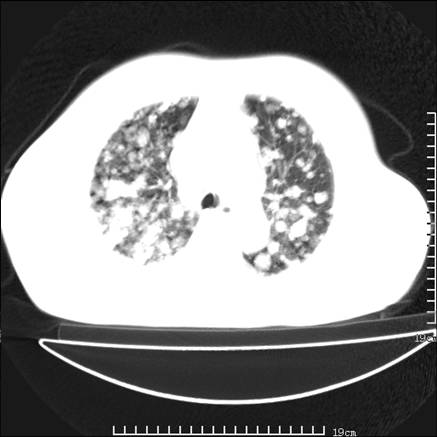

张男,75岁,干咳半年余,小便不利二年,b超检查前列腺增大,未见明显肿块;前列腺癌血生化检查多项指标明显增高。

双肺内多发转移瘤,纵膈淋巴结转移。来源前列腺?建议盆腔mri进一步检查。

双肺转移满了。

两肺广泛转移瘤。